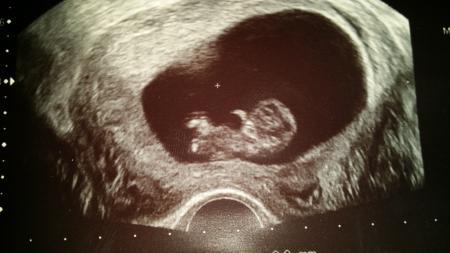

Jeka26

Ui wie fein...man sieht auch schon fein was nech... :-) Hatte meins schonmal gepostet... aber hier gerne nochma in die Bilderunde

Bild zu